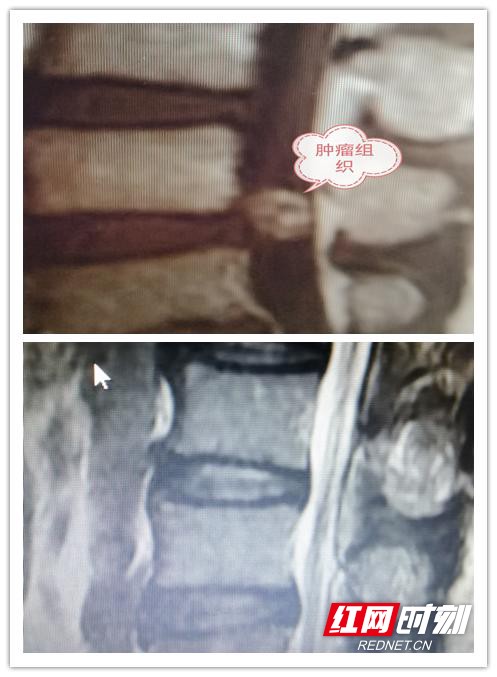

患者术前术后检查影像。

51岁的徐伯是家里的主要劳动力,3个月前出现腰痛、腿麻症状。开始以为是腰间盘突出并未太多干预,但随着时间推移情况愈加严重,几乎丧失劳动能力。经过省级医院检查,发现椎管内长了一个花生米大小的肿瘤,建议施行开放手术,手术费用需要十余万,且术后不能从事重体力工作。这一消息让本不富裕的家庭雪上加霜,实在凑不齐医药费,徐伯一家只得回到钱粮湖老家。

经与家属沟通后,黎建先组织医生团队为徐伯设计了手术方案。术中,医生在显微镜下经微通道操作,术野清晰,不需要打钉内固定,不切除脊椎骨,仅仅3个小时就完整切除肿瘤,患者神经功能未受到任何损伤。术后第2天徐伯即可行走自如,术后第4天病人出院,总费用2.5万余。徐伯不禁感叹:“想不到在我们岳阳,就有和北京、上海一样的先进医疗技术,家门口就能够治好大病。”